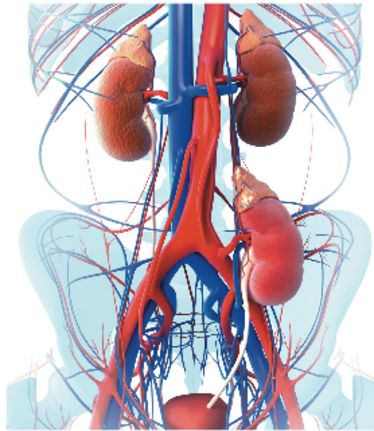

24.05.2014

9. Münsteraner Gefäßtage

9. Münsteraner Gefäßtage

24.05.2014

9. Münsteraner Gefäßtage

9. Münsteraner Gefäßtage